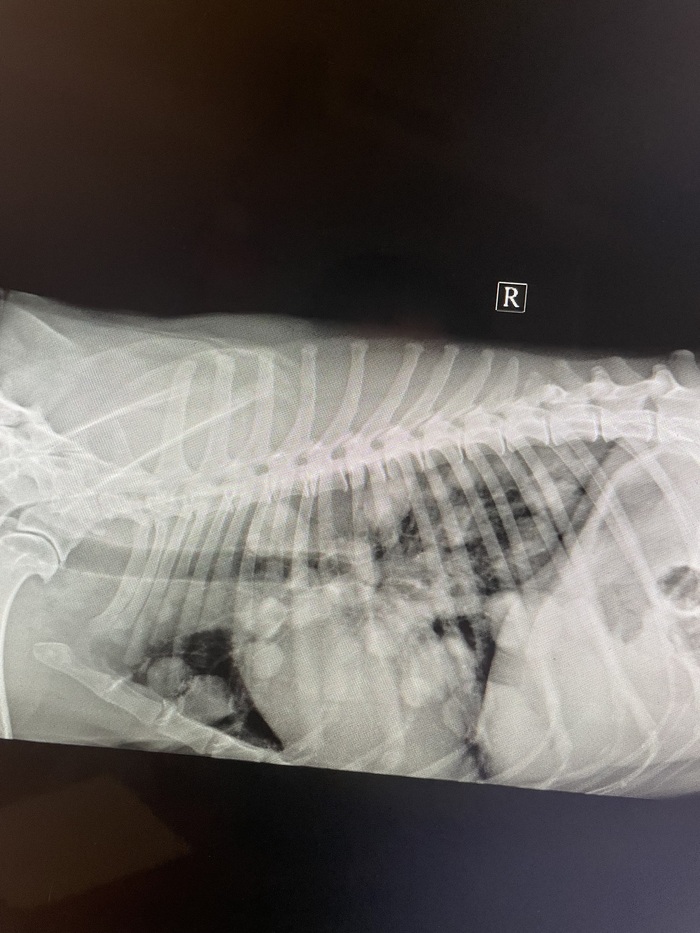

Дано: возрастная кошка с длительным ринитом.

Пришли на прием 13.10 с формулировкой «гноится глазик». Я увидел их 14.10 и всё же уговорил пойти на кт, а там абсцесс за левым глазом, фронтит (забиты и лобные пазухи, и носовые ходы).

После проводим фронтотомию - по сути, бурим дырку в лобную пазуху для промывания и вымывания всего скопившегося гноя.

Промыв всё большим количеством тёплого стерильного физ.раствора, зашиваем всё. Плюсом удаляем назофарингеальный полип.